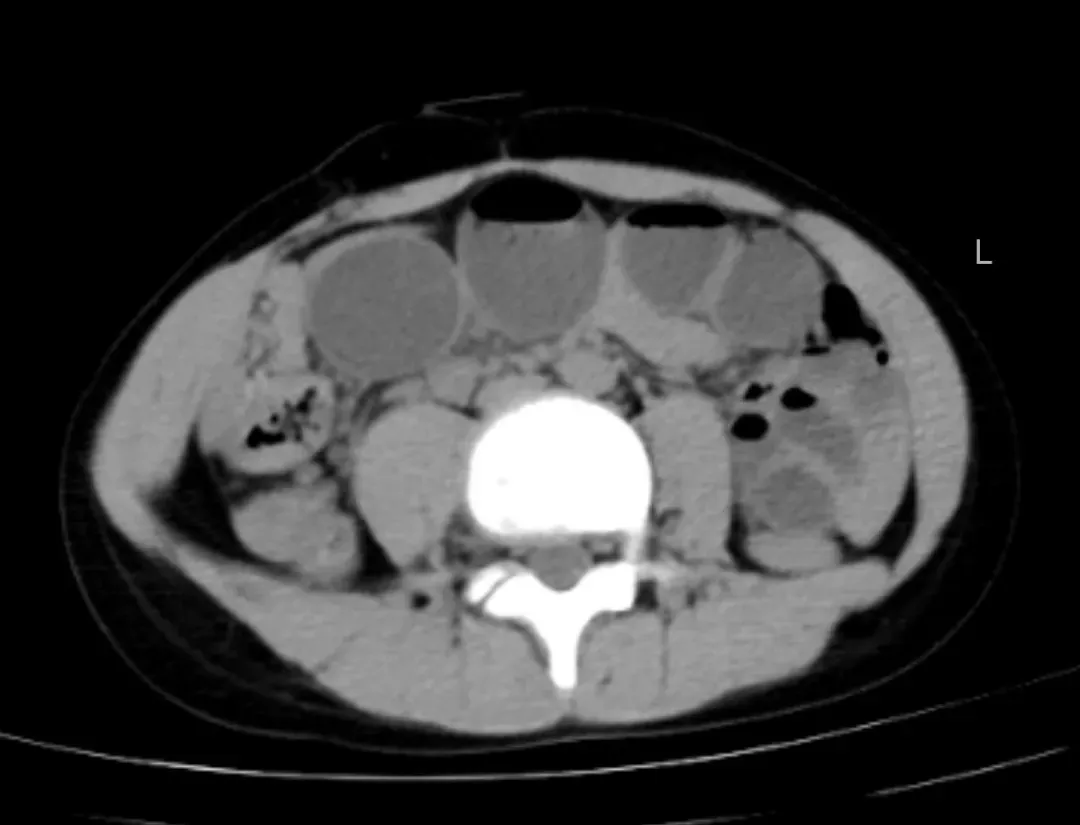

近日,一场由“甜蜜冬枣”引发的健康危机在延安市中医医院(北京大学第三医院延安分院)儿科上演,一名10岁患儿在食用大量冬枣后,突发剧烈腹痛、呕吐伴腹胀,腹部CT提示胃内大量内容物堆积,伴发小肠梗阻征象,情况危急。儿科潘维伟主任与屈晖副主任根据明确的饮食史与影像依据,快速诊断为极为罕见的“植物性胃结石并发肠梗阻”。

入院影像检查